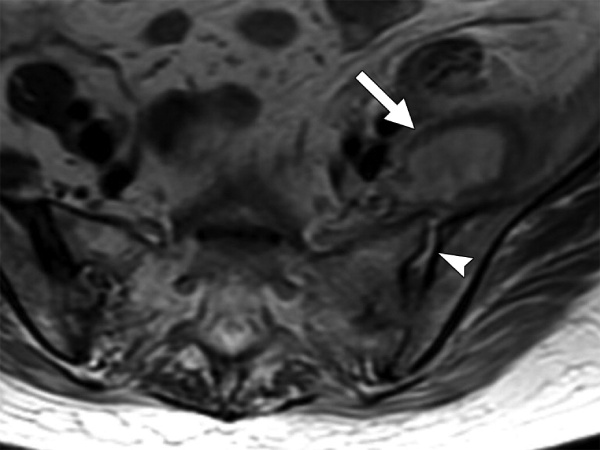

Kết quả chụp cộng hưởng từ cho thấy mức độ tổn thương của khớp cùng chậu, cơ, dây chằng, vết nứt gãy nhỏ tại khớp. Với phương pháp này, bác sĩ có thể chẩn đoán mức độ viêm của khớp cùng chậu từ giai đoạn khởi phát mà chụp X Quang và CT không phát hiện được.